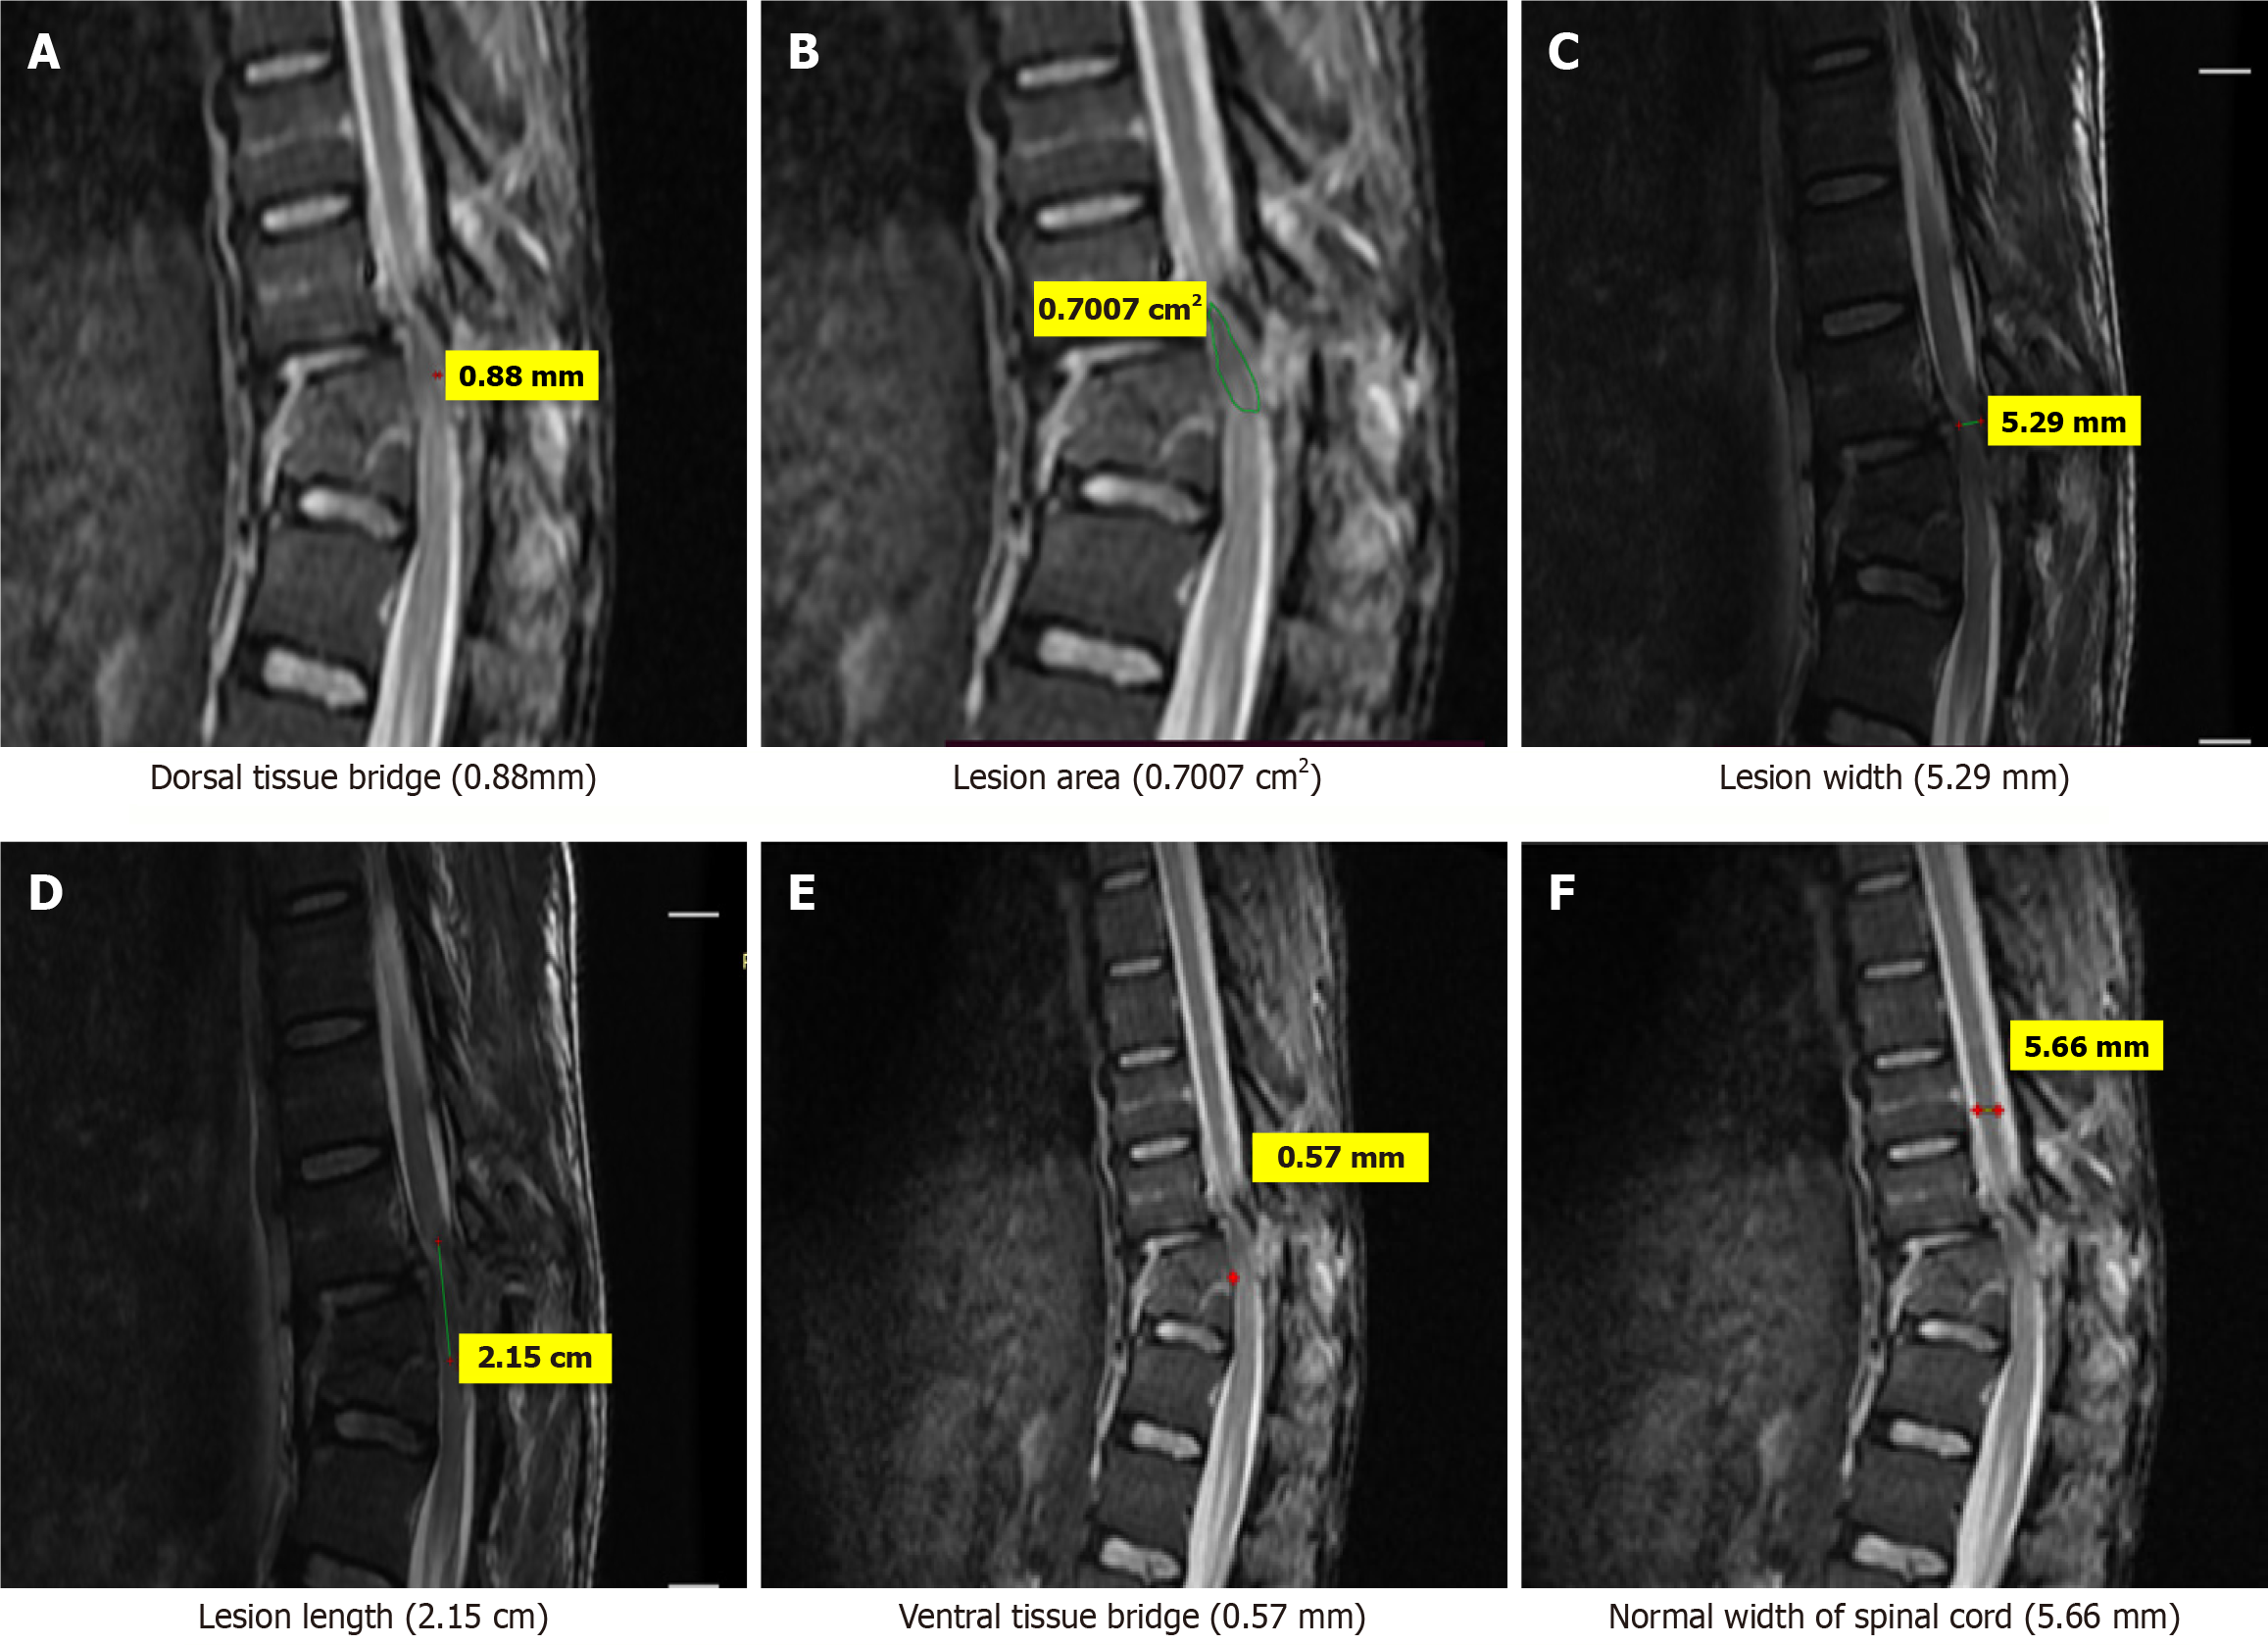

Figure 2 Magnetic resonance imaging T2-weighted sagittal images of a 30-years old patient who sustained trauma to thoracic spine(D11) with ASIA grade C.

A: Dorsal tissue bridge (0.88 mm); B: Lesion area (0.7007 cm2); C: Lesion width (5.29 mm); D: Lesion length (2.15 cm); E: Ventral tissue bridge (0.57 mm); F: Normal width of spinal cord (5.66 mm).